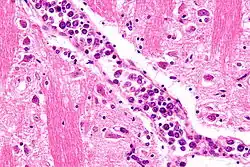

| Micrograph showing an intravascular large B-cell lymphoma in a blood vessel of the brain. H&E stain. | |